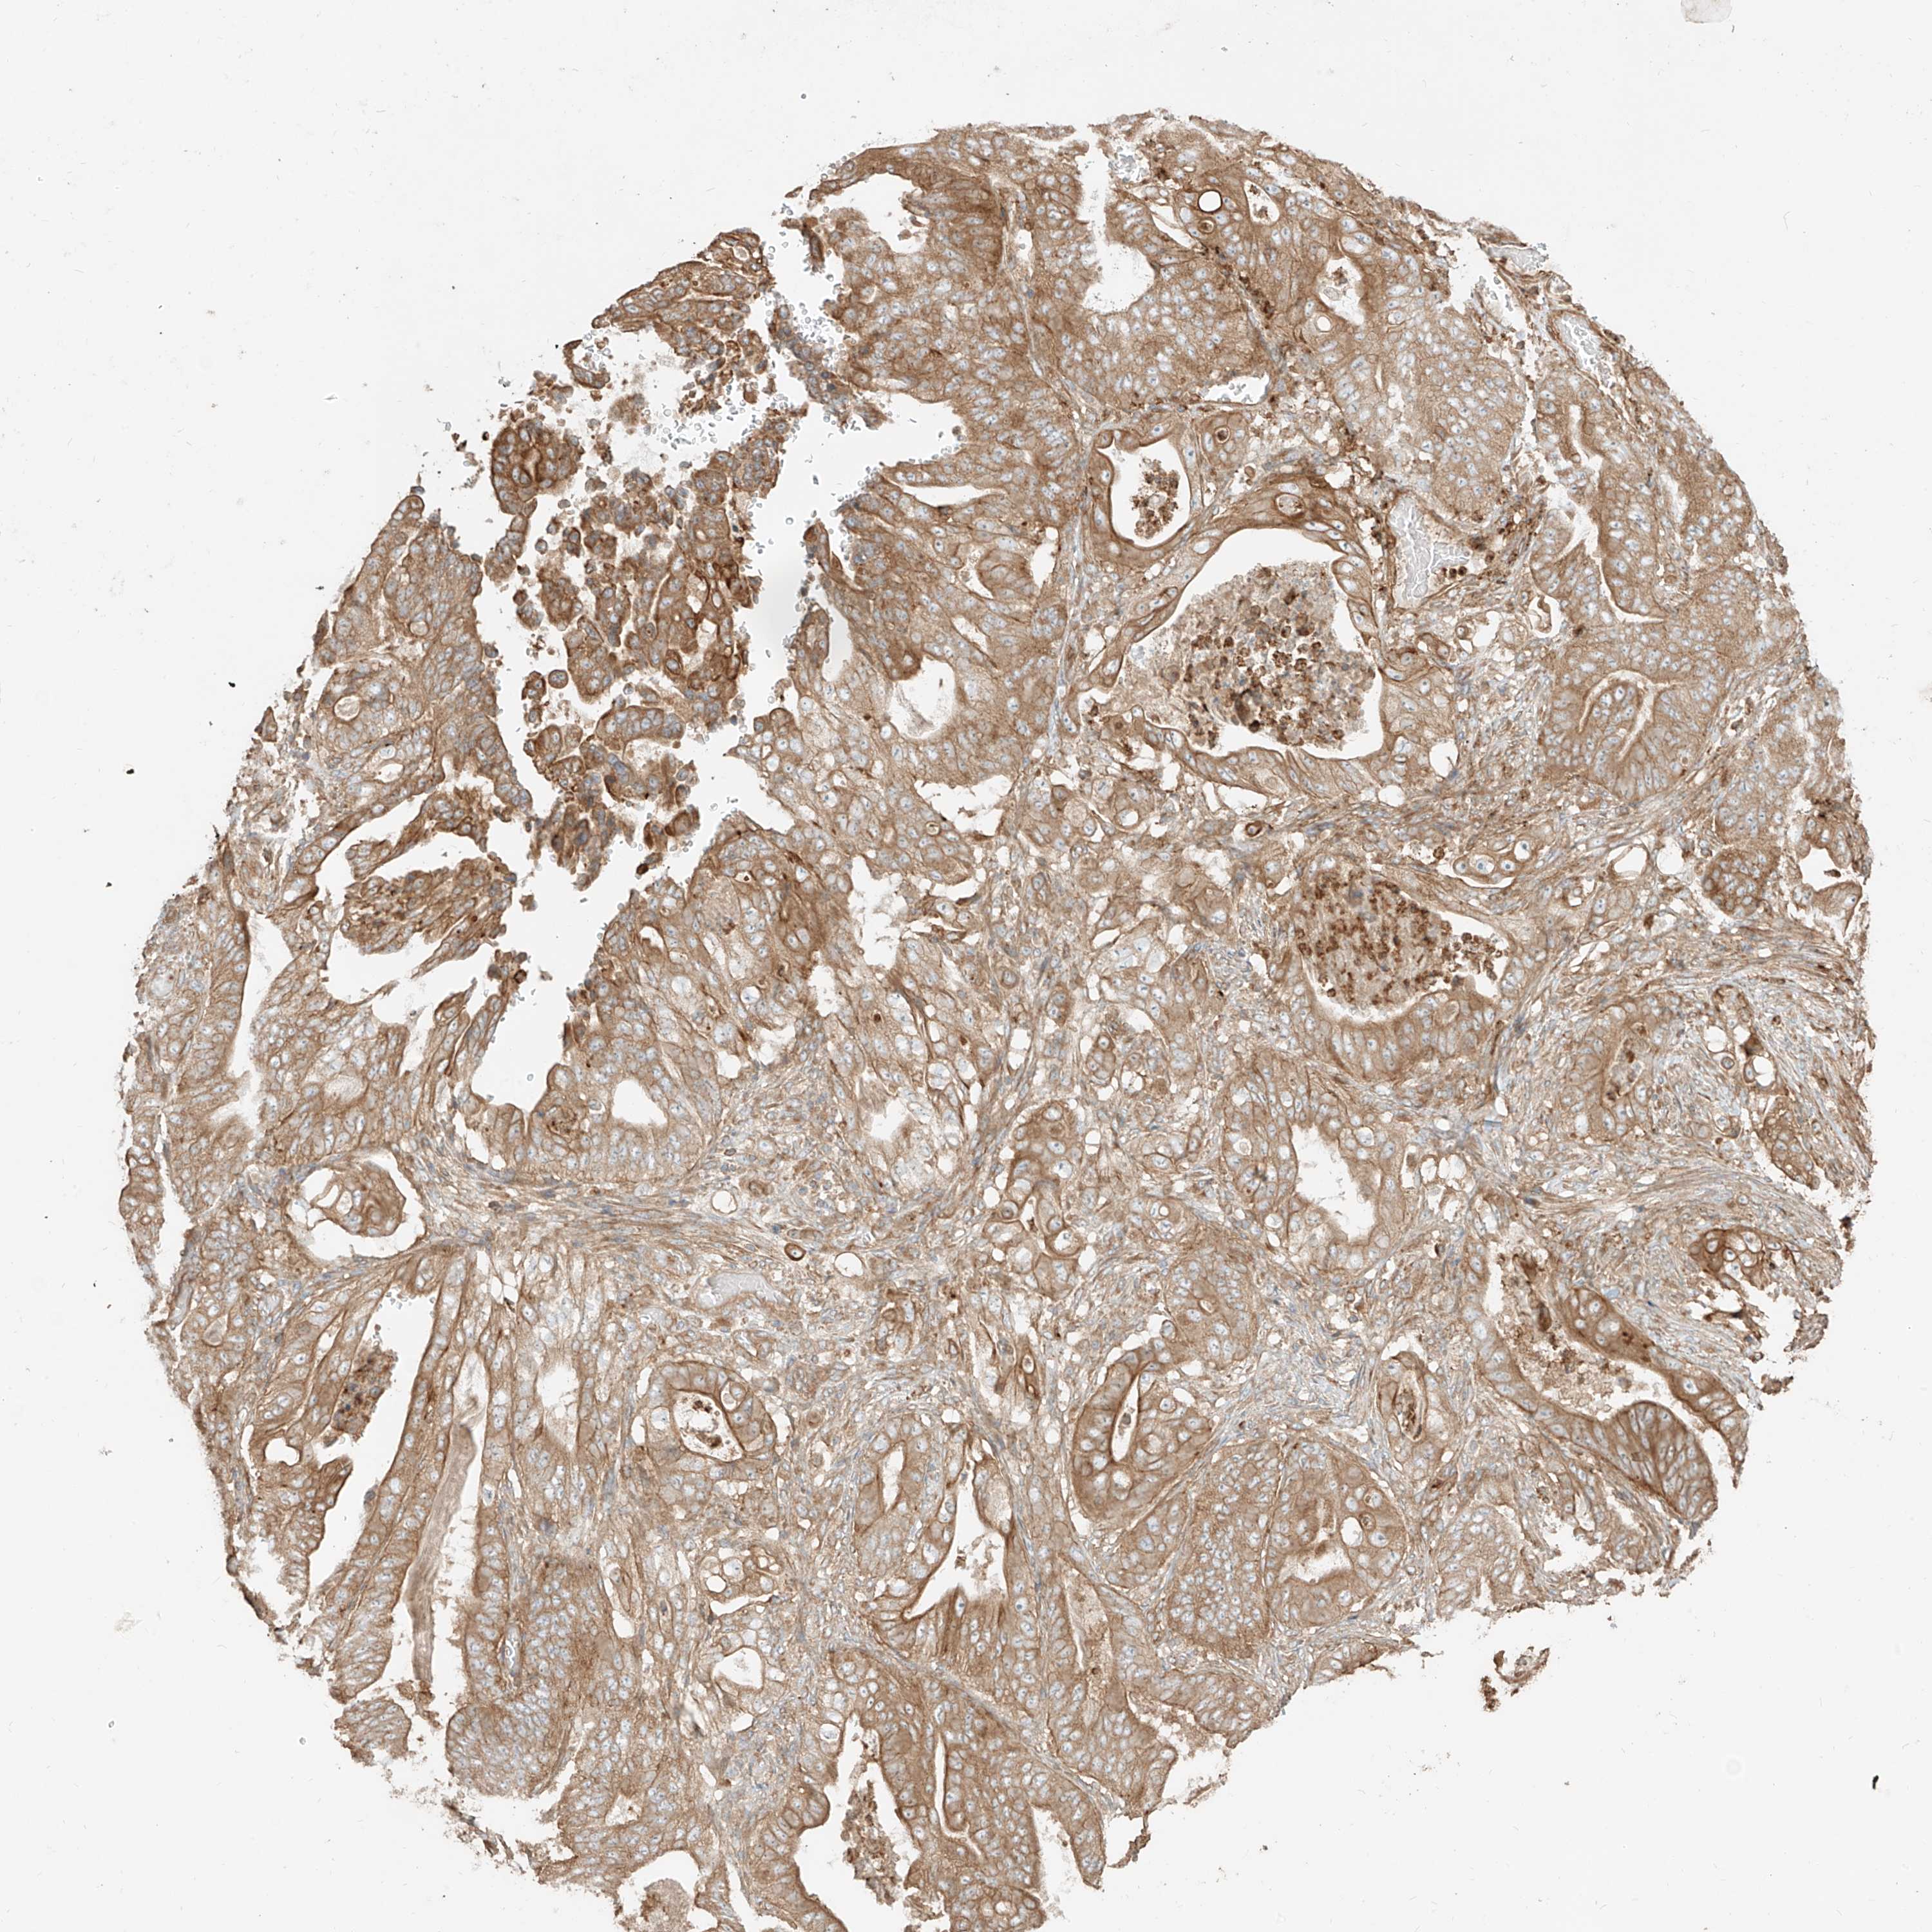

STOMACH CANCER - Protein expressioni

A mouse-over function shows sample information and annotation data. Click on an image to view it in a full screen mode. Samples can be filtered based on level of antibody staining by selecting one or several of the following categories: high, medium, low and not detected. The assay and annotation is described here.

Note that samples used for immunohistochemistry by the Human Protein Atlas do not correspond to samples in the TCGA dataset.

Antibody stainingi

Antibody staining in the annotated cell types in the current human tissue is reported as not detected, low, medium, or high, based on conventional immunohistochemistry profiling in selected tissues. This score is based on the combination of the staining intensity and fraction of stained cells.

Each image is clickable and will lead to virtual microscopy that enables deeper exploration of all samples and also displays staining intensity scores, fraction scores and subcellular localization as well as patient and tissue information for each sample.

Antibody HPA034598

Staining

High

Medium

Low

Not detected

Intensity

Strong

Moderate

Weak

Negative

Quantity

>75%

75%-25%

<25%

None

Location

Nuclear

Cytoplasmic/membranous

Cytoplasmic/membranous,nuclear

Adenocarcinoma, NOS